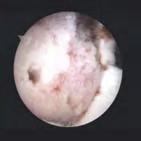

Rozpoznanie

Wywiad i badanie kliniczne